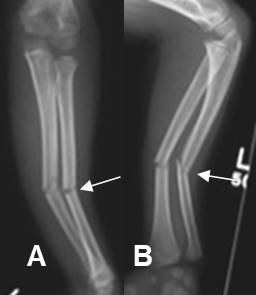

Fig 65. Fractura en leño verde.

A: Rx AP y B: Rx lateral. Fracturas en leño verde del radio y cúbito con rotación y angulación anterior y en valgo.